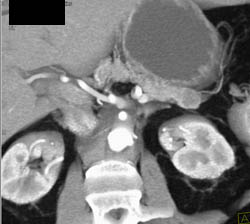

Diagnosis

Intraductal Papillary Mucinous Neoplasm (IPMN)